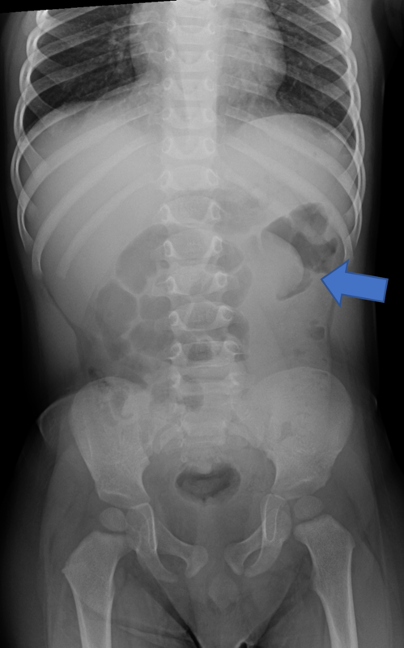

While opsoclonus-myoclonus-ataxis (dancing eye-dancing feet syndrome) may seem rare and complex, its early identification in the ED can be life‑altering. When faced with an unusual movement disorder a